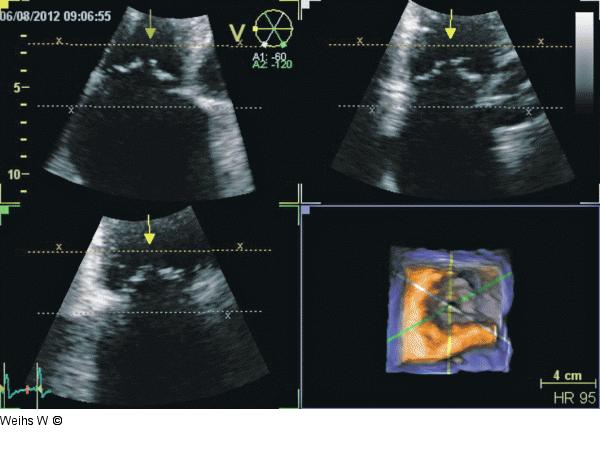

Abbildung 4: Trikuspidalsegel Zweidimensionale Schnitte aus dem 3D-Echo. Es ist eine eindeutige Orientierung und Zuordnung der drei Trikuspidalsegel möglich. |

Zweidimensionale Schnitte aus dem 3D-Echo. Es ist eine eindeutige Orientierung und Zuordnung der drei Trikuspidalsegel möglich. |